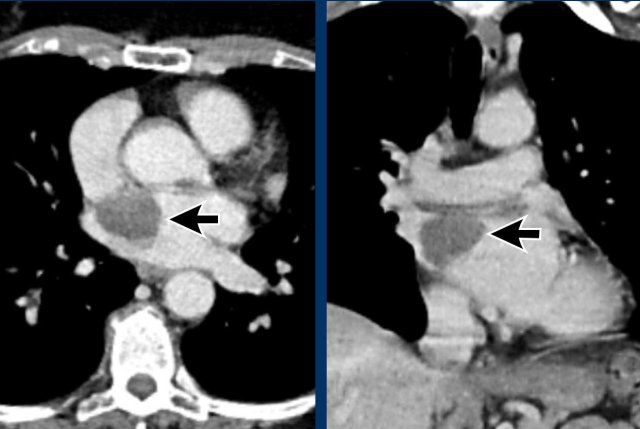

Image

Post myocardial infarction in LAD territory with apical aneurysm formation, wall calcification and a large intraventricular thrombus.